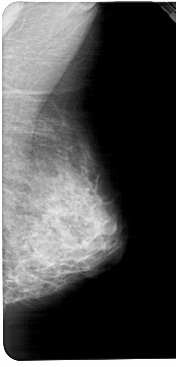

A_1459_1.LEFT_MLO

LEFT_MLO LINES 5386 PIXELS_PER_LINE 2521 BITS_PER_PIXEL 12 RESOLUTION 43.5 OVERLAY